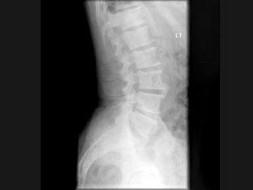

问题 男,77岁,全身性骨痛,夜间加重,贫血,PSA大于100,结合图像,最可能的诊断是?(?)

选项 A.成骨性骨转移 B.多发性骨髓瘤 C.慢性化脓性骨髓炎 D.骨肉瘤 E.以上都不是

答案 A